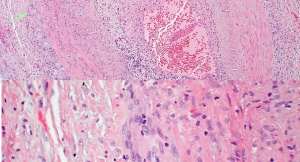

Then, in 1932, Bayard Horton reported two patients presenting with symptoms that would eventually be highly characteristic of giant cell arteritis, including fever, weakness, headache, pain, difficulty chewing, transient diplopia, and vision loss.[3] Horton and his team were the first to perform a temporal artery biopsy and describe the now well-known histopathological findings of granulomatous vasculitis. At the time, the disease was known as “Horton’s disease.” The pathology of the disease was further explained by Gilmoure in 1941, when he described the presence of giant cells as part of the disease. The term “temporal arteritis” began to gain popularity in the 1930s and was further linked to other inflammatory and rheumatological diseases such as polymyalgia rheumatica (PMR) by Jennings in 1938.[4] Current literature estimates that approximately one-third of patients with GCA have PMR at presentation.

Giant cell arteritis is characterized by a nodular granulomatous inflammation of medium- and large-sized arteries (Figure 1).[31] Pathological examination of affected vessels usually reveals a fragmented internal elastic lamina, with a cellular infiltrate extending transmurally.[32] Skip lesions are common, so typically a 2 cm biopsy of the temporal artery is recommended. Giant cells are not necessary to confirm the diagnosis; however, when they are present, they are most often situated near the fragmented internal elastic membrane.[33] The most commonly affected vessels are the superficial temporal artery, the ophthalmic artery, the posterior ciliary arteries, and the vertebral arteries.[34] Less commonly, the aorta, coronary arteries, and carotid circulation are involved; intracranial arteries are usually spared.[33] The intracerebral arteries are also typically spared from the vasculitic attack of GCA, presumably because of the paucity of elastic tissue in their walls.[27]

All biopsy sections should be stained with hematoxylin and eosin. Staining for elastin using an elastic Van Gieson stain has been proposed in order to identify the internal elastic lamina; however, a 2010 retrospective case series studying 105 biopsies showed no increase in diagnostic sensitivity using this method. Van Gieson staining may be helpful in cases of supplementary investigation, such as repeat biopsies.[90]

Most commonly, a panarteritis consisting of lymphocytes and macrophages with or without granuloma formation is seen during inspection. Additionally, intimal thickening and fragmentation of the internal elastic lamina should be sought. The procedure for obtaining a temporal artery biopsy is relatively safe, with rare reports of complications (e.g., hematoma, infection, nerve damage, stroke, scalp necrosis).[71][91][92][93]